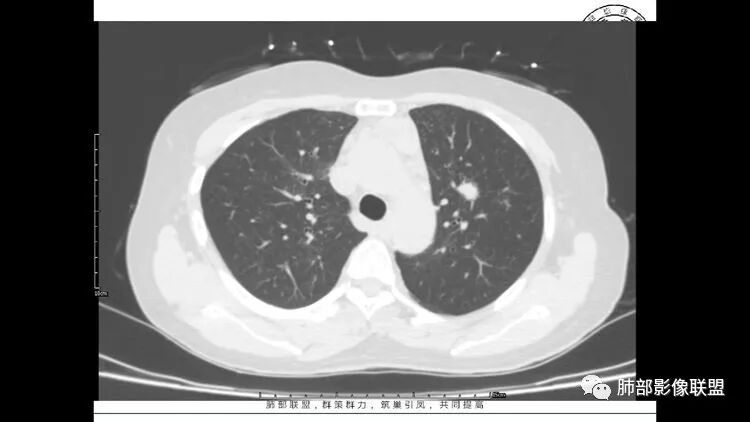

老年女性,眼炎入院,血常规正常,双肺多发囊状影,病变随机分布,形态单一,与血管关系密切,考虑LIP。左下肺混合GGO,边界尚清,贴近囊腔,鉴别腺癌。炎症指标无异常暂不考虑感染性病变。

胸CT:1.双肺多发囊性变,以中下肺为主,病变边缘可见肺动脉,部分囊内可见分隔及肺动脉,双下部分肺野周围可见小叶中心结节及树丫征。

2 左肺上叶尖后段 右肺上叶前段 右肺下叶外基底段 结节影,边界清楚,可见柔软毛刺,左肺下叶后基底段混合密度影。

3.纵隔淋巴结肿大?,以主动脉弓为界向上向下增大。

考虑:淋巴瘤肺浸润,眼部症状考虑与此有关;LIP?;继续鉴别肺腺癌?血管炎?。

双肺多发磨玻璃结节,其内可见空腔,周围边界清晰,多发囊,左肺实性结节。考虑间质性肺炎,LIP可能性大。鉴别腺癌。

患者中年女性,因右眼红痛1天就诊。胸CT:双肺多发囊性变及结节影,囊以中下肺为多,部分囊内可见分隔及肺动脉,结节部分为实性,部分为混合性,边缘光滑,未见明显毛刺、棘突、胸膜牵拉及血管集束征象。双中下可见支气管扩张及树丫征。淋巴结无明显肿大。综合考虑:一元淋巴细胞间质性肺炎。多元鉴别肺腺癌并转移等恶性病变。

中年女性,双肺多发囊性变,以中下肺为主,病变边缘可见肺动脉,部分囊内可见分隔及肺动脉,左肺上叶较大结节,可见分叶、月牙铲,左肺下叶、右肺中叶磨玻璃病灶,边界清楚,内有空泡,结节,可见尖后段 右肺上叶前段 右肺下叶外基底段 结节影,边界清楚,纵隔淋巴结肿大,

考虑腺癌,淋巴管肌瘤病?LIP?

中年女性,因“角膜炎”入院,自用眼液2年,(眼干?)肺部:双肺多发类圆形薄壁气囊+实性结节+GGO,下肺分布为主,纵隔淋巴结肿大,考虑淋巴系统增殖,LIP可能性大,可能继发于干燥综合症;左肺下叶的混合磨玻璃结节形迹可疑,边界清晰,内部疑似空泡,扩张扭曲支气管,极像肺癌,伴双肺转移?待排吧

LIP影像重要线索一句话:

双肺下叶分布为主的间质改变(磨玻璃影、小叶间隔增厚)、散在气囊影(常有血管贴边)、边界不清小结节